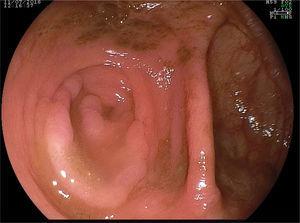

A 55-year-old man had unremarkable personal and family histories. Due to a positive fecal occult blood test, he underwent a video colonoscopy that identified multiple (more than 40) flat, elevated polyps (Paris classification 0-IIa) from 10 to 50mm in diameter, and predominating in the right colon (figs. 1 and 2). Magnification chromoendoscopy with acetic acid at 3% was performed (figs. 3 and 4), providing a better definition of the polyps. The anatomopathologic study of one of them reported serrated adenoma with no cytologic dysplasia (fig. 5).

In accordance with the WHO definition, serrated polyposis syndrome (SPS) was diagnosed due to the presence of more than 20 serrated polyps of any size distributed throughout the colon.

Given the multiplicity of the large lesions that were predominant in the right colon and the topography of one of them at the level of the appendicular orifice, conditioning its endoscopic resectability, the joint decision among surgeons was made to perform a right hemicolectomy, as well as resection by mucosectomy of the polyps described in detail in the left colon.